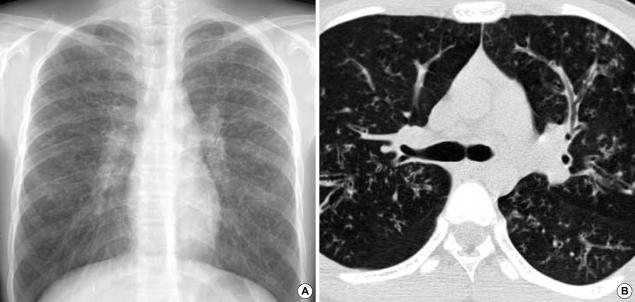

Although cystic fibrosis (CF) is one of the most frequently seen autosomal-recessive disorders in Caucasians, it is extremely rare in the Korean population. Recently, a 15-yr-old Korean boy was admitted to our hospital complaining of coughing, sputum, and exertional dyspnea. Chest radiographs and computed tomographic chest and paranasal sinus scans revealed diffuse bronchiectasis and pansinusitis. Pulmonary function tests revealed severe obstructive impairment. The average sweat chloride concentrations on both of the patients' forearms were 63.0 mM/L (reference limit: < 40 mM/L). Upon mutation analysis, two different mutations (Q98R and Q220X) were identified in the cystic fibrosis transmembrane conductance regulator gene, both of which had been previously detected in CF patients, one from France and the other from England. As CF is quite rare in Korea, the diagnosis of CF in this patient might be delayed. Therefore, we recommend that a diagnosis of CF should be suspected in patients exhibiting unexplained chronic respiratory symptoms.

尽管囊性纤维化(CF)是白种人中最常见的常染色体隐性疾病之一,但在韩国人群中极为罕见。最近,一名15岁的韩国男孩因咳嗽、咳痰和劳力性呼吸困难入院。胸部X光片以及胸部和鼻旁窦计算机断层扫描显示弥漫性支气管扩张和全鼻窦炎。肺功能测试显示严重的阻塞性损害。患者双侧前臂汗液氯化物平均浓度为63.0 mM/L(参考限值:<40 mM/L)。经突变分析,在囊性纤维化跨膜传导调节基因中鉴定出两种不同的突变(Q98R和Q220X),这两种突变先前已在CF患者中检测到,一个来自法国,另一个来自英国。由于CF在韩国相当罕见,该患者的CF诊断可能会延迟。因此,我们建议对出现无法解释的慢性呼吸道症状的患者怀疑CF诊断。